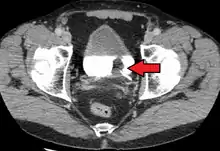

| Transitional cell carcinoma of the bladder. The white in the bladder is contrast. | |

Bladder cancer is any of several types of cancer arising from the tissues of the urinary bladder.[1] Symptoms include blood in the urine, pain with urination, and low back pain.[1] It is caused when epithelial cells that line the bladder become malignant.[4]

Risk factors for bladder cancer include smoking, family history, prior radiation therapy, frequent bladder infections, and exposure to certain chemicals.[1] The most common type is transitional cell carcinoma.[1] Other types include squamous cell carcinoma and adenocarcinoma.[1] Diagnosis is typically by cystoscopy with tissue biopsies.[5] Staging of the cancer is determined by transurethral resection and medical imaging.[1][6][7]